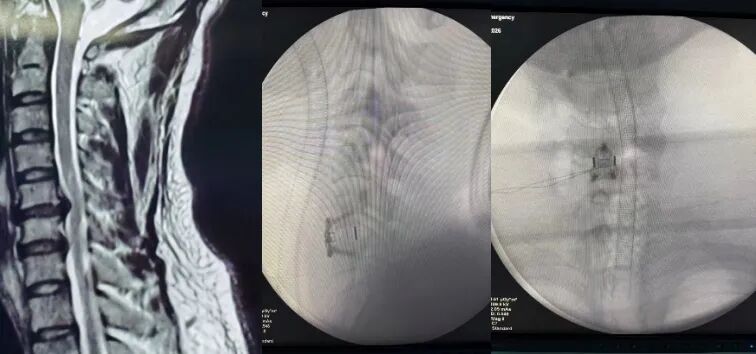

58岁的女性患者因C6/C7节段巨大颈椎间盘突出压迫脊髓,出现四肢麻木及肌力下降,龚福太团队通过颈椎前路手术,精细切除突出椎间盘,解除脊髓压迫,并运用椎间植骨融合与钢板内固定技术重建颈椎稳定性,术后患者的神经症状得到显著改善。

脊柱手术被称为“刀尖上的舞蹈”,颈椎手术更是重中之重,稍有不慎便可能损伤神经、血管,导致患者终身瘫痪。在这台颈椎手术中,龚福太凭借丰富的临床经验,在切除突出物的过程中密切观察患者反应,每一个操作都精准谨慎,确保神经功能不受损伤。